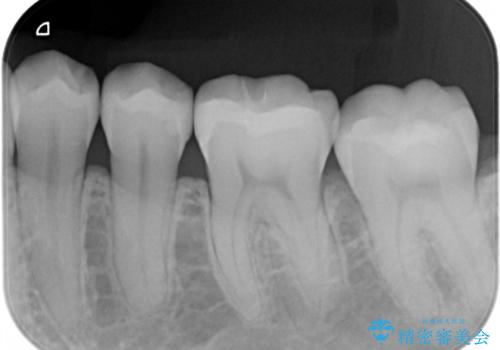

- 矯正治療が終了して歯並びが綺麗になると、元々入っていた銀歯が気になってきたとのことで適合の良いセラミックへのやり替えを行いました。

適合不良の補綴物は二次的な虫歯発生のリスクが高まります。

自費診療で用いられる材料は保険適応の材料に比べて、より精密で適合の良い被せ物作ることができるため、長期的な虫歯のリスクを大幅に減らすことが可能です。